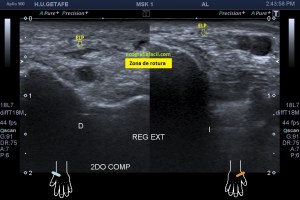

Paciente que acude derivado del traumatólogo por una sospecha rotura del extensor del pulgar. Cuando posicioné al paciente para iniciar la exploración y le hice el interrogatorio habitual, me contó que desde un traumatismo donde se rompió las dos muñecas, tiene una incapacidad para estirar completamente el dedo pulgar a la altura de la interfalángica, no de la metacarpofalángica.

Lo que me llamó la atención fue que la parte superficial del segundo compartimento, correspondiente con el extensor largo del pulgar cruzando por encima del compartimento 2, era que estaba muy hipoecogénica y grande, así que una vez comprobado que los dos tendones del compartimento eran normales, y sabiendo que el tercero pasa por encima para cruzarse buscando el primer dedo, lo que hice fue seguir el tercer compartimento y lo que ví era que estaba situado en su lugar junto al tubérculo de lister, proximalmente, que a su cruce por encima del compartimento dos, estaba hipoecogénico y gordo y que ya en la mano, por donde cruza buscando el primer dedo, no estaba o al menos no estaba íntegro.

En este recorrido encontré un muñón, que se observa perfectamente en longitudinal, y que correspondía con el extensor largo del pulgar a la altura de su recorrido.

3

En esta imagen quiero que te fijes en el segundo compartimento y como el extensor largo del pulgar pasa por encima, los dos tendones del compartimento dos cortados en eje corto y el del tercero, cortado, pero en un corte para-axial. Lo importante es que te fijes en la ecogenicidad de ELP, en la izquierda hiperecogénico, isoecogénico con el segundo compartimento, por tanto normal. En la derecha hipoecogénico y más gordo, patológico.

4

Seguimos avanzando hacia distal, seguimos observando las mismas diferencias en las imágenes comparativas. Imagen justo antes de la rotura.

5

En la rotura el tendón es muy pequeño, pero normal en la izquierda y en la derecha lo es igual de pequeño, pero aplanado y con la pérdida de la ecogenicidad normal.

6

Después de la rotura, avanzando a distal, el tendón retraído, hipoecogénico, mucho más grande que su comparativo contralateral.

7

Corte en eje largo correspondiente a la imagen 6, donde se ve claramente lo que pasa y es definitivo para el diagnóstico final.

En resumen, desde la imagen 3 a la 8 observas el recorrido ecográfico del tendón extensor del pulgar desde proximal hasta distal, pasando por el foco de rotura y terminando con el muñón en axial y en longitudinal según marcan los pictogramas.